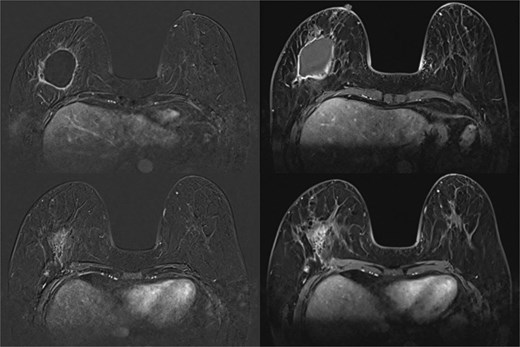

MRI breast showed seroma from excision biopsy and delayed enhancement in the anterior aspect of the collection that may represent residual disease (Fig. 8). She underwent breast conserving surgery to obtain clear margins, and sentinel node biopsy. Wide excision histology showed residual 13 mm invasive carcinoma with clear margins and one lymph node positive on sentinel node biopsy. She subsequently underwent axillary clearance and completion nipple-sparing mastectomy and reconstruction with free deep inferior epigastric perforator (DIEP) flap (Fig. 9). Histology revealed no residual carcinoma and further nodal metastasis. She underwent adjuvant chemotherapy, targeted therapy and radiotherapy. She has remained well 3 years after her surgery and continues to be screened for cancer annually with a MRI for her contralateral breast.